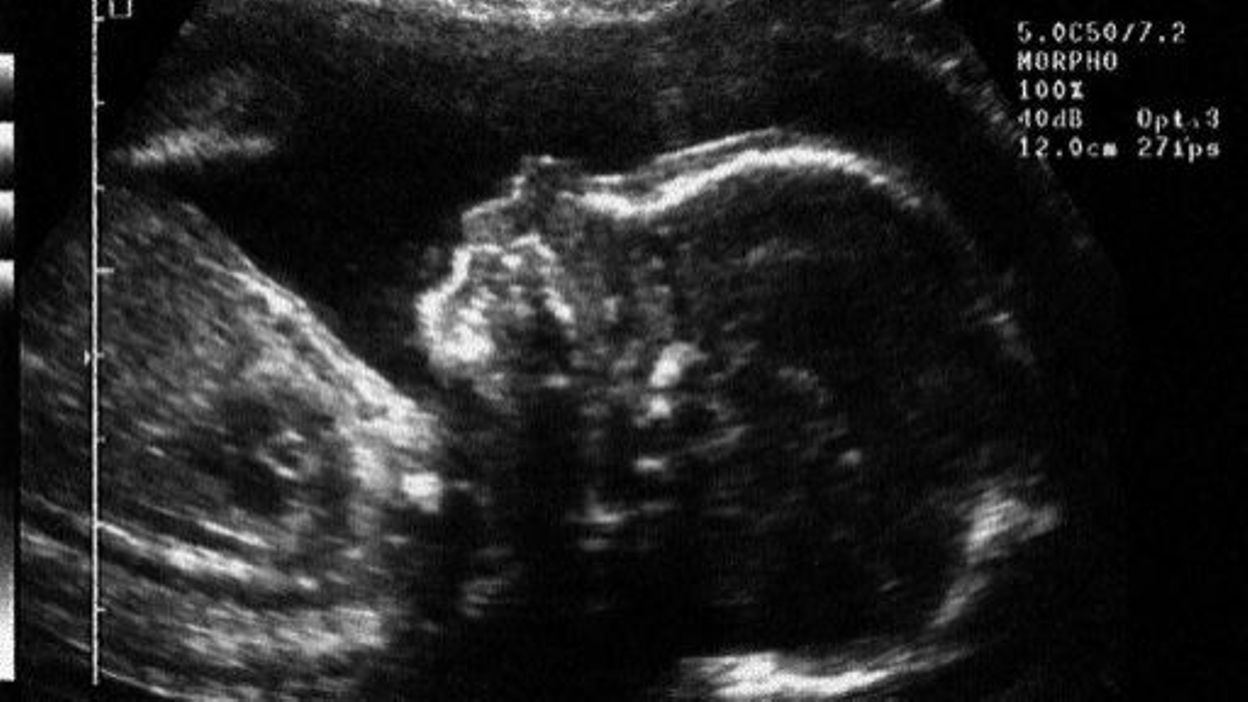

Bonjour, ma soeur est enceinte de 8semaines elle a vue son gygy ya 2 jrs son embryon est de 4mm ce qui est pas normal d'apré lui,et il é pas arrivé a entendre ses battements de coeur mais.

Mais là encore, c'est souvent lors d'une échographie que l'on s'aperçoit que le cœur du fœtus ne bat plus.

Si la grossesse se passe sans problème, le cœur du bébé pourra ensuite à nouveau être entendu aux trois autres échographies planifiées avant l'accouchement.

Diverses circonstances, comme un placenta antérieur, peuvent également augmenter la difficulté d’entendre le cœur du fœtus.

Cela ne signifie pas pour autant qu’il ne.

Lors de l’échographie, vous pourrez écouter le cœur de votre bébé pendant quelques minutes à l’aide d’un appareil à ultrasons.